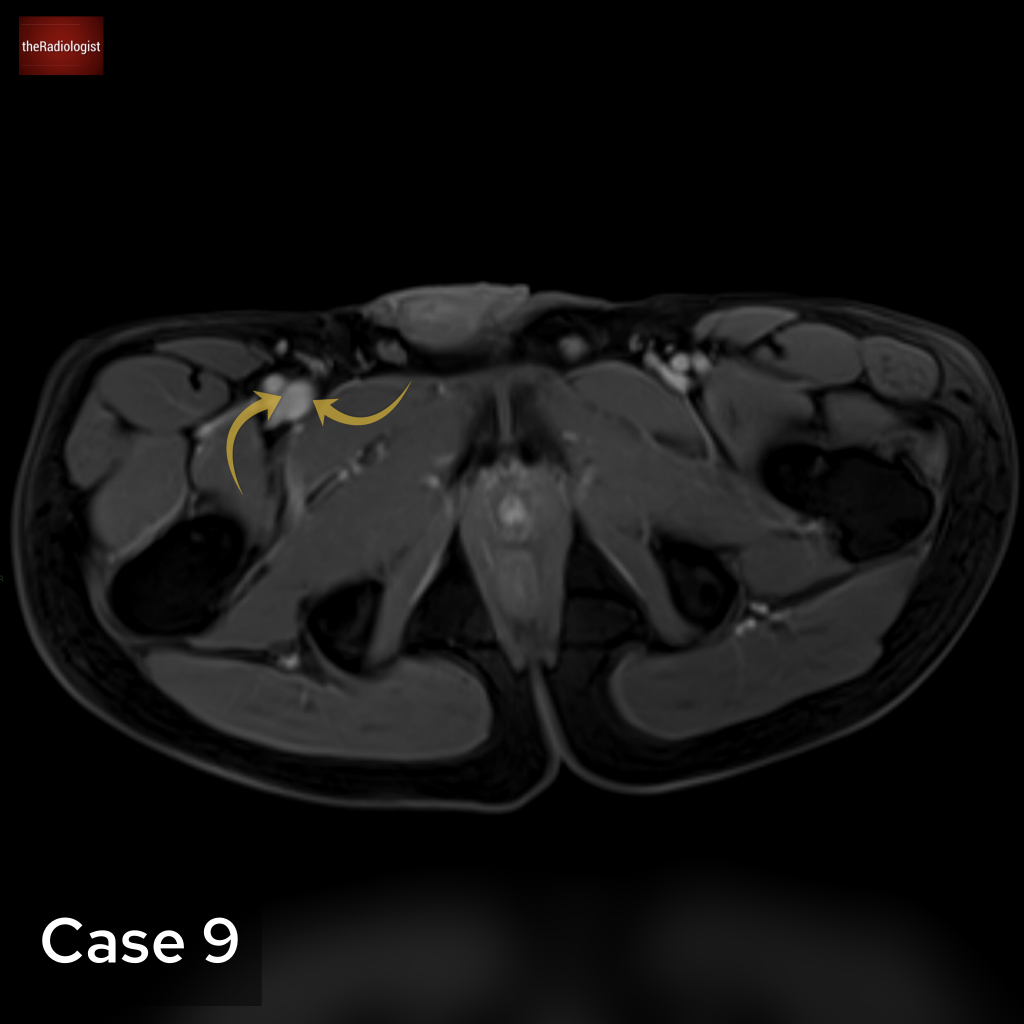

Case 9

Here e are looking at a pelvic MRI image. What are the arrows pointing at?

Choose from one of the following: